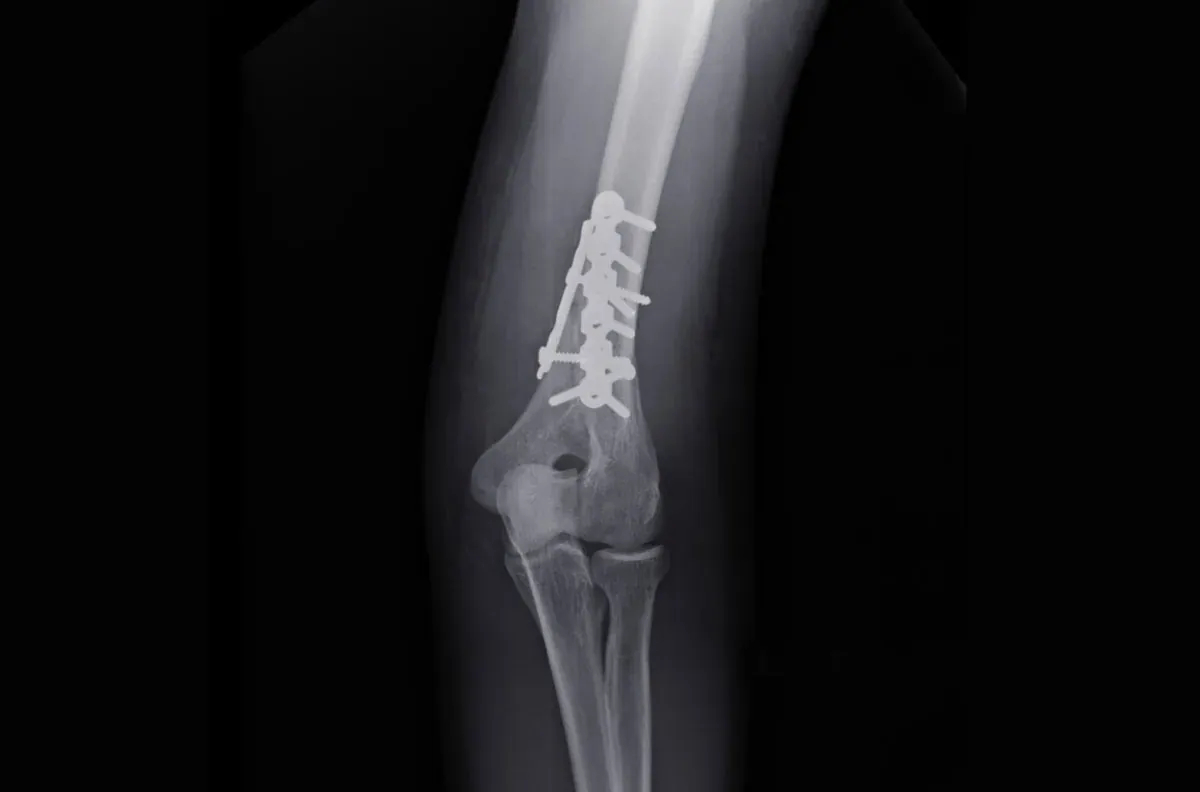

- Metoda leczenia: Czy zastosowano leczenie zachowawcze (gips, orteza) czy operacyjne (płytki, śruby, gwoździe).

Po leczeniu operacyjnym, kiedy złamanie zostało stabilnie zespolone wewnętrznie (np. za pomocą płytek i śrub), rehabilitację można i wręcz należy rozpocząć bardzo wcześnie. Często zdarza się, że pierwsze ćwiczenia wykonujemy już w pierwszej lub drugiej dobie po zabiegu, jeszcze zanim pacjent opuści szpital. Celem tych wczesnych działań jest przede wszystkim poprawa krążenia, zapobieganie groźnym zakrzepom, minimalizowanie obrzęków i przykurczów, a także utrzymanie zakresu ruchu w stawach sąsiadujących z miejscem operacji, które nie są bezpośrednio unieruchomione.

Stabilizacja wewnętrzna, czyli zastosowanie płytek, śrub, gwoździ czy drutów, to prawdziwy przełom w leczeniu złamań. Dzięki niej odłamki kostne są utrzymywane w anatomicznym położeniu, co nie tylko sprzyja prawidłowemu zrostowi, ale przede wszystkim pozwala na znacznie wcześniejsze i bezpieczniejsze rozpoczęcie ruchu. W przeciwieństwie do leczenia zachowawczego, gdzie gips całkowicie unieruchamia kończynę na długie tygodnie, stabilizacja wewnętrzna daje możliwość kontrolowanego obciążania i mobilizacji, co znacząco skraca czas rekonwalescencji i minimalizuje ryzyko utraty funkcji.